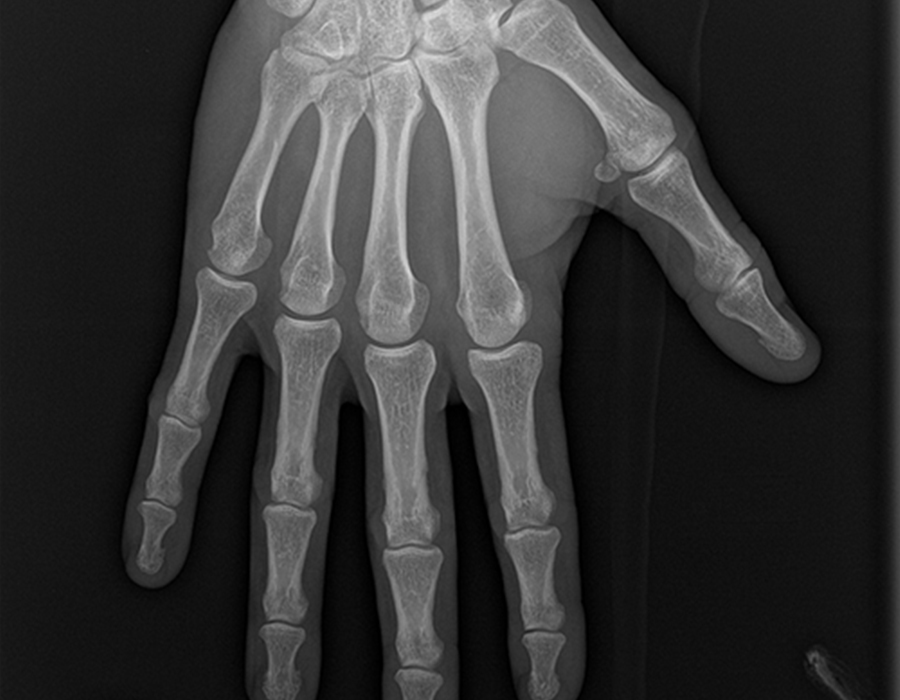

Radiographie du rachis dorsolombaire Radiographie du rachis lombaire Radiographie du rachis dorsal Radiographie du rachis cervical Radiographie de l'abdomen sans préparation Radiographie du gril costal Radiographie colonne lombaire et bassin Scanner des sinus. Charnière thoracolombaire translation in FrenchEnglish dictionary fr Rachis lombaire et charnières thoracolombaire et lombosacrée raideur active et gêne douloureuse pour tous les mouvements en toutes positions nécessitant une thérapeutique régulière douleurs très fréquentes avec gêne permanente requérant des précautions lors de tous les mouvements avec raideur segmentaire. Lombaire definition in French dictionary, lombaire meaning, synonyms, see also 'lobaire',lombardien',lombalgie',lombard' Enrich your vocabulary with the French Definition dictionary.